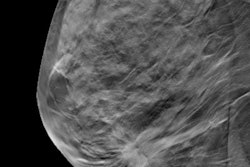

Dalhblom et al wanted to evaluate commercially available AI software (Transpara version 1.7.0, ScreenPoint Medical) and find out if it could detect additional cancers on digital mammography screening which would otherwise only be identified on DBT or be undetected and later appear as interval cancers.

They looked at data from 14,768 Swedish women in the Malmö Breast Tomosynthesis Screening Trial. The average age of the women was 57 years. Of the 136 cancers found, 95 were detected on 2D digital mammography and 41 were detected only on DBT.

The highest examination risk score was assigned to 1,493 breast exams, about 10.1% of the total patient cohort. The AI system detected 71 of the digital mammography-detected cancers. Of the cancers that radiologists detected on DBT only, 18 were detected by the AI system, 17 of which were invasive.

"The results of this study suggest that, in an optimal scenario, when all AI detected cancers are found, the cancer detection rate on digital mammography per 1,000 women could be increased from 6.4 to 7.7 using AI," the study authors wrote. "This would reduce the gap to DBT (8.7) and could be more feasible than DBT screening."